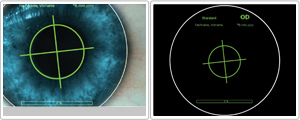

· 수술 중 실시간으로 안구가 회전하는 정도를 microscope안의 십자축의 위치변화로 확인가능하며, 안구회전현상(Cyclotorsion)을 실시간으로 추적하여 정확한 난시축에 레이저를 조사하여 난시교정이 뛰어납니다.